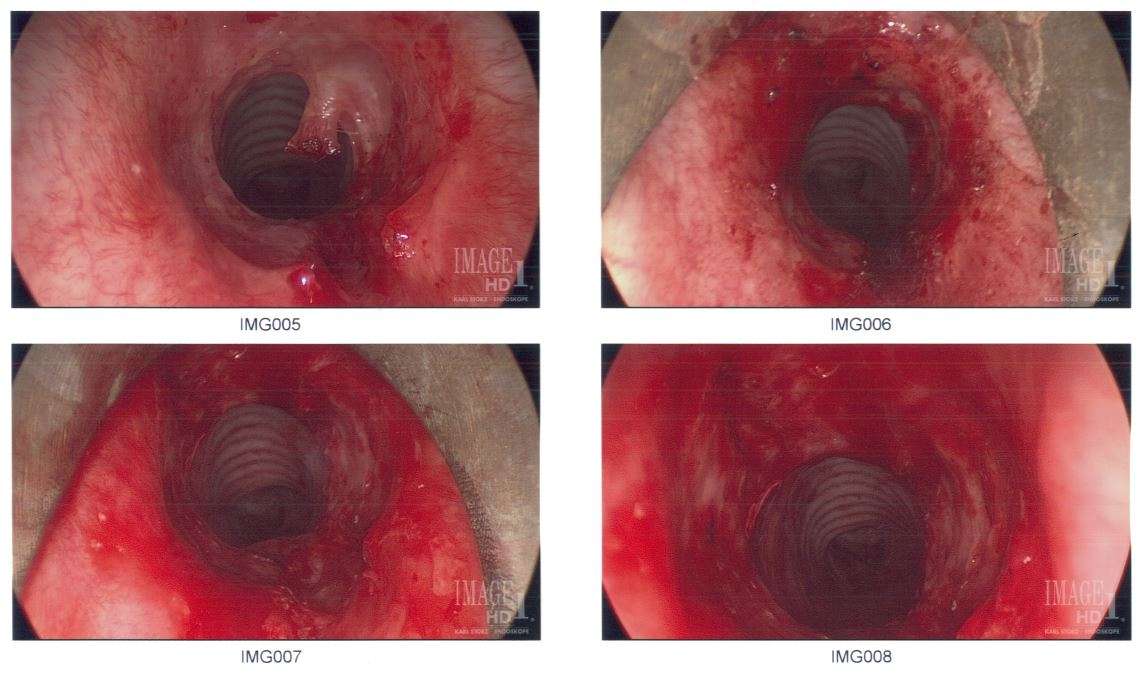

Subglottic stenosis is a congenital or acquired narrowing of the subglottic airway. Although it is relatively rare, it is the third most common congenital airway problem (after laryngomalacia and vocal cord paralysis). Subglottic stenosis can present as a life-threatening airway emergency. It is imperative that the otolaryngologist be an expert at dealing with the diagnosis and management of this disorder. Subglottic stenosis can affect both children and adults.

Subglottic stenosis can be of three forms, namely congenital subglottic stenosis, idiopathic subglottic stenosis (ISS) and acquired subglottic stenosis. As the name suggests, congenital subglottic stenosis is a birth defect. Idiopathic subglottic stenosis is a narrowing of the airway due to an unknown cause. Acquired subglottic stenosis generally follows as an after-effect of airway intubation, and in extremely rare cases as a result of gastroesophageal reflux disease (GERD).

Subglottic stenosis is graded from one to four based on the severity of the block.

Grade 1 - <50% obstruction, Grade 2 - 51-70% obstruction, Grade 3 - 71-99% obstruction, Grade 4 - no detectable lumen.